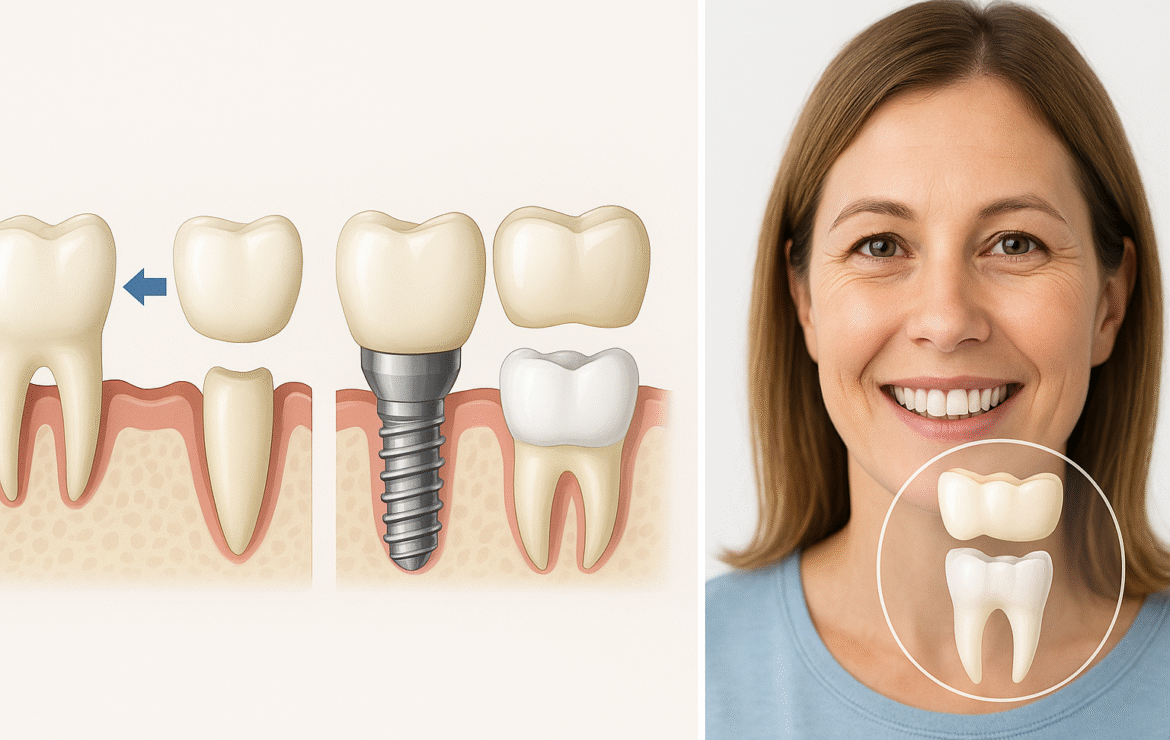

أولًا: الزراعة السنية (Dental Implant) — الخيار الذهبي

ما هي؟ جذع تيتانيومي يُثبَّت داخل عظم الفك كجذر صناعي، ثم تُركَّب دعامة وتاج خزفي يُحاكي السن الطبيعي.

المزايا:

يحافظ على العظم ويمنع امتصاصه.

لا يستلزم برد أسنان مجاورة سليمة.

ثبات عالي وإحساس أقرب للطبيعي في المضغ والنطق.

المدّة العامة: من 8–12 أسبوعًا عادة لالتحام الزرعة بالعظم قبل تركيب التاج (تختلف حسب الحالة).

ثانيًا: الجسر الثابت (Fixed Bridge)

ما هو؟ تاجٌ يُثبَّت على السنّين المجاورين للفراغ ليحمل سنًا تعويضيًا وسطهما.